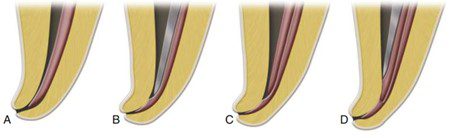

– Côn chính không đưa đến hết chiều dài làm việc thì là quá lớn (kẹt trước chiều dài làm việc). Còn côn chính có thể đẩy quá chiều dài làm việc thì là quá nhỏ (không kẹt tại chiều dài làm việc, dẫn đến trám quá chóp).

– Côn chính không có kháng lực khi rút ra cũng là quá nhỏ (không vừa khít tại chiều dài làm việc), mặc dù cảm giác này có thể khó phát hiện.

– Cần kiểm tra kỹ để phát hiện côn bị cong khi đặt đến chiều dài làm việc và rút ra; điều này cho thấy côn không phù hợp. Côn cong gần đầu có thể là quá nhỏ.

Côn cong ở phần thân hơn có thể là quá lớn (có vẻ đặt đến chiều dài làm việc vì kìm gắp chạm điểm tham chiếu, nhưng côn sẽ ngắn do cong).